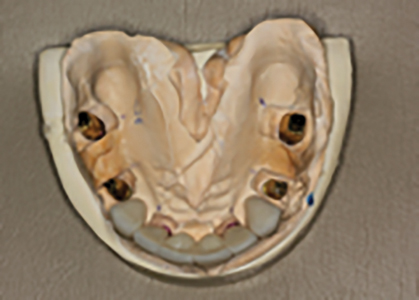

The final treatment plan would require implants in the #16, 14, 12, 22, 24 and 26 positions. The fixed provisional prosthesis would make use of provisional abutments on #17 and 27, 13, 23 and 11. The plan would involve serial extractions and grafting procedures to preserve bone volume in the ideal sites while avoiding any load on the newly grafted sites using strategic teeth to serve as provisional abutments. Patient accepted this solution and agreed to keep teeth #13 and #23. Benefits include cuspid rise occlusion, bone preservation and proprioception (also to minimize the significant risk with adjacent implants in the anterior zone).

- N.B. Existing #17 to be converted to #16, existing #16 to be converted to #15 and 14, existing #26 to be converted to #24 and 25. Lastly #27 will be converted to 26.

- Prepare #17, 27 13, 11 and 23 and provisionalization.

- Extraction of #16, 12, 22 and 26. (Socket grafting #16, and 26 to preserve existing bone volume).

- Immediate implant placement in sites #12, 22, 14 and 24.

- Reassess healing clinically and radiographically over a 4-6 month healing period.